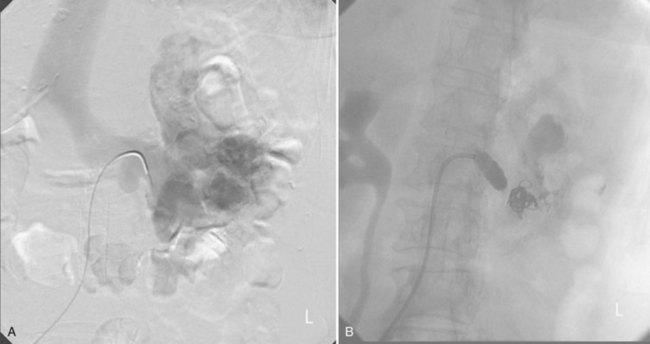

Since its introduction in the early 1970s, renal artery embolization (RAE) has been employed for palliation of inoperable renal tumors, to control bleeding, and as part of multimodal treatment of hypervascular metastatic disease (Almgard et al, 1973). In addition, RAE is used as a preoperative adjunct to resection of locally advanced renal tumors, with or without metastases (Paster et al, 1975) (Fig. 54–15).

Figure 54–15 A, Aortogram in a patient with a left hypervascular renal mass. Note the pooling of contrast medium in the upper pole. B, Left selective artery angiogram before coil placement. C, Aortogram after coil placement demonstrating abrupt cutoff of flow from the left renal artery.

Proposed benefits of preoperative RAE include shrinkage of an arterialized tumor thrombus to ease surgical removal, reduced blood loss, facilitation of dissection due to tissue plane edema, ability to ligate the renal vein before the renal artery at time of nephrectomy, and modulation of the immune response (Klimberg et al, 1985; Bakal et al, 1993; Kalman and Varenhorst, 1999; Schwartz et al, 2007; Wotkowicz and Libertino, 2007; Wszolek et al, 2008). Ligation of the renal vein before the renal artery is useful in the setting of hilar tumors, tumors with significant medial extension, or considerable perihilar adenopathy (Schwartz et al, 2007; Wotkowicz and Libertino, 2007; Wszolek et al, 2008). Before ligating the renal vein, one should characterize the completeness of embolization to prevent unnecessary blood loss in cases of incomplete embolization. In the senior author’s experience this assessment can be made by evaluating renal venous return during surgery. In addition, angioembolization can also be useful for renal tumors associated with large arteriovenous malformations that are having a deleterious hemodynamic impact (Figs. 54-16 and 54-17).

Figure 54–16 Noncontrast (A) and contrast-enhanced (B) CT images of a patient with high output cardiac failure secondary to arteriovenous malformation associated with left renal cell carcinoma. Notice the equal contrast intensity of the aorta, left renal artery, and left renal vein.

Figure 54–17 A, Left selective renal angiogram demonstrates immediate filling of the renal vein and inferior vena cava. B, Angiogram after placement of coils demonstrates complete angioinfarction. Contrast medium in the contralateral renal pelvis confirms contralateral renal function.

There may be a survival benefit to preoperative RAE. In a case-control study, preoperative RAE and nephrectomy was associated with a survival benefit when compared with nephrectomy alone (Zielinski et al, 2000). In comparison to matched controls, preoperative RAE was associated with improved overall survival at 5 years (62% vs. 35%, P = .01) and 10 years (47% vs. 23%, P = .01). This possible survival benefit has not been demonstrated in a prospective trial.

The postinfarction syndrome, which is characterized by flank pain, nausea, and fever, occurs in approximately three fourths of patients and is the most frequently cited complication of RAE (Schwartz et al, 2007). Other complications, including incomplete embolization, coil migration, and groin hematoma, occurred in fewer than 5% of patients (Schwartz et al, 2007). Rarely cited complications include hyponatremia (Huang et al, 2003), paraplegia due to occlusion of spinal arteries, or inadvertent angioinfarction of other organs such as the colon (Roy et al, 1999).

The data regarding preoperative RAE are limited, without any randomized trials evaluating the technique. As a result, in some institutions, surgeons rarely employ preoperative RAE (Boorjian et al, 2007). It is the practice of the senior author to perform preoperative RAE for large renal tumors with hypervascular characteristics or IVC tumor thrombus (Wotkowicz and Libertino, 2007). The ideal timing of nephrectomy after embolization is unclear (Craven et al, 1991; Weckermann et al, 1992; Kalman and Varenhorst, 1999; Schwartz et al, 2007). At the Lahey Clinic, surgery usually is timed 4 weeks after angioinfarction. An imaging study to assess the cranial limit of tumor thrombus is repeated shortly before the operation. Although prospective trials are needed to evaluate the role of preoperative RAE in the treatment of renal cell carcinoma, the senior author has found it a useful preoperative adjunct in the management of locally advanced RCC.